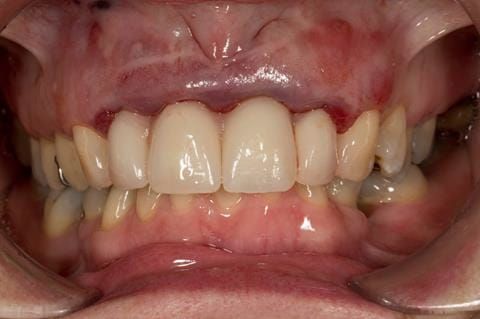

- High smile line showing gum above gingival zeniths of upper front teeth when smiling. Aesthetic failure of the upper four incisors with inflammation of the gingivae and mis-match of the gingival zenith levels.

- Other than the maxillary incisors the remaining dentition was in marginally better condition being moderately to heavily restored. Many will probably require replacement and restoration from time to time mainly from wear and tear owing to occlusal forces.

Following consultation and second discussion appointment the patient chose to have option 3 namely, a maxillary cobalt chromium based partial denture/protective occlusal splint. The clinical situation and treatment process is shown in detail below with photographs. The patient was successfully rehabilitated with this and her quality of life considerably improved. The clinical work was provided by Finlay and the technical work by Rowan.